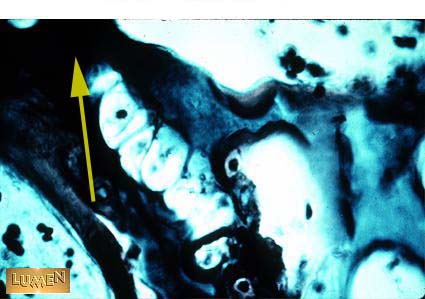

What happened to this cartilage?

Calcification